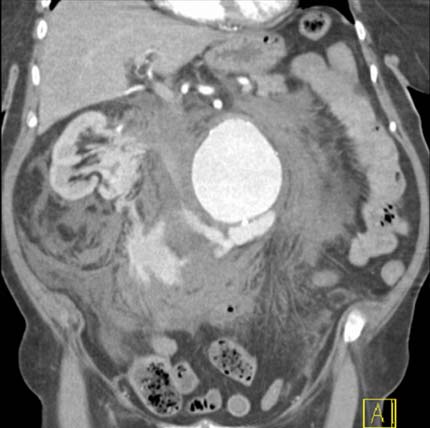

A CT scan showing a ruptured abdominal aorta.

Note: Images are shown for illustrative purposes. Do not attempt to draw conclusions or make diagnoses by comparing these images to other medical images, particularly your own. Only qualified physicians should interpret images; the radiologist is the physician expert trained in medical imaging.